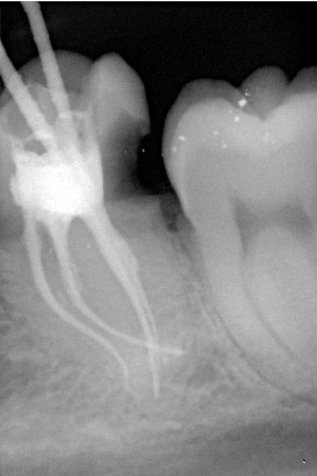

Unter örtlicher Betäubung ist die Behandlung in der Regel schmerzfrei. Nach Entfernung der Karies und nach der Schaffung eines Zugangs in den Zahn werden die Kanaleingänge dargestellt und die Länge jedes einzelnen Kanals wird möglichst exakt unter Anwendung von Röntgen ausgemessen. Abhängig vom zu behandelten Zahn kann die Anzahl der Kanäle stark variieren.

Mit Hilfe der elektronischen Längenmessung und digitalen Röntgenbildern können die Länge und Krümmung der Kanäle bestimmt und der Verlauf beurteilt werden.

Kanalaufbereitung